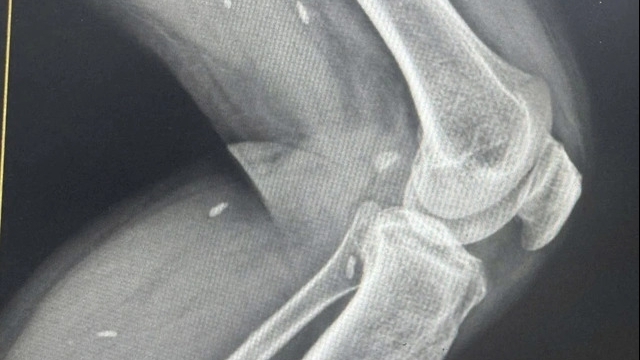

| Khoảng 8h sáng 30/6, sản phụ Nguyễn Thị Tình (37 tuổi, trú huyện Can Lộc, mang thai đủ tháng) có dấu hiệu chuyển dạ, được đưa vào Bệnh viện Đa khoa huyện Đức Thọ. Tại đây, bác sĩ thăm khám và cho biết cổ tử cung của sản phụ Tình đã mở 4 cm, tim thai và sức khỏe hoàn toàn ổn định, chờ sinh thường. Đến 18h30, chị Tình bắt đầu đau dữ dội, bác sĩ thăm khám, cho hay tử cung đã mở hết và đưa lên bàn đẻ. 19h20 cùng ngày, chồng chị Tình nhận được thông báo của ê-kíp y bác sĩ là con đã tử vong với vết đứt dài trên cổ. Bệnh viện Đa khoa huyện Đức Thọ báo cáo Sở Y tế Hà Tĩnh rằng thai nhi đã chết lưu trên 3 ngày. Đến ngày 2/7, Sở Y tế Hà Tĩnh có báo cáo gửi Bộ Y tế về vụ việc, nhưng lại khẳng định thai nhi chết lưu trên 7 ngày. Công an huyện Đức Thọ vào cuộc điều tra và đề nghị Sở Y tế Hà Tĩnh thành lập Hội đồng chuyên môn đánh giá lại toàn bộ quy trình vụ việc song sở này chưa thực hiện và chờ kết quả điều tra. |